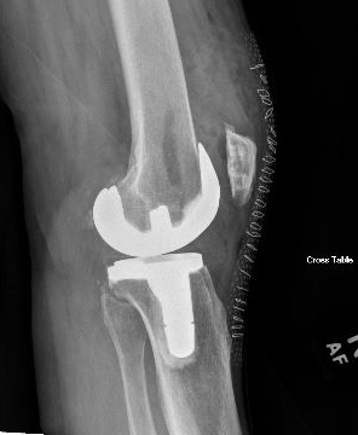

Example X-Ray Images

Knee Replacement

A surgical procedure performed to replace worn joint surfaces in the knee, usually due to severe arthritis. An incision is made on the front of the knee and the worn joint surfaces are removed. Metal components are then cemented on the tibia and femur. A spacer made of a specialized plastic is placed in between the tibia and femur. The surface of the knee cap is also removed and replaced with a plastic button. When all of the components are in place the knee is checked to ensure appropriate range of motion, alignment, and stability.

A total knee replacement is a replacement of the three compartments of the knee (patellofemoral, medial, and lateral) with metal and a plastic spacer in between. There are three components to the replacement – a metal end of the femur and tibia, and a polyethylene spacer.

What are knee replacements made of?

Knee replacements are made of metal alloy such as cobalt chromium. The spacers in between the metal components are made of polyethylene.